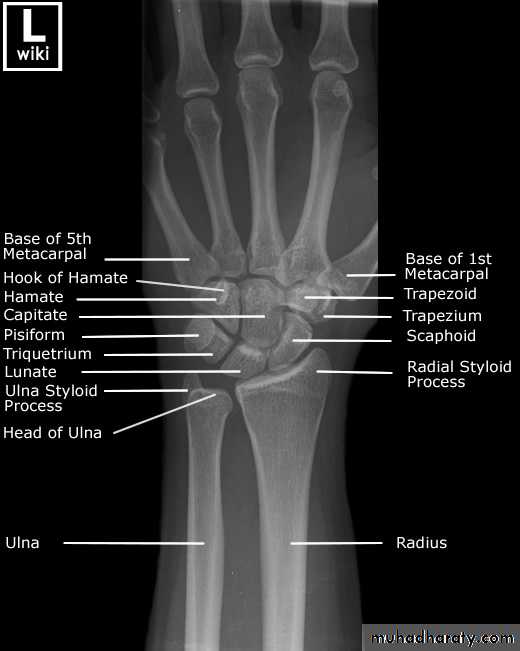

• تقدير العمر من العظام: يستطيع الطبيب ان يقدر العمر بدرجة لاباس بها من الدقة فيما بين الولادة وحتى سن 25 عاما من خلال فحصه المراكزالتعظمية المختلفة وبخاصة تلك التي تظهر في الطرف العلوي, والتي غالبا ما نفضلها على غيرها وذلك لسهولة تحريك الطرف العلوي وبمدى واسع بحيث يتحكم به المصور الشعاعي. يعتمد الطبيب في تقدير العمر على ظهور او التحام مراكز التعظم او كلاهما لمجموعة من العظام, حيث ان هناك اوقات محدد لظهور هذه المراكز والتحامها.

• عمليا يتم تصوير الرسغ والمرفق والكتف لمن يبدوا ظاهرا دون سن العشرين عاما من العمر. ويصور الحرقف لمن بدا في اواسط العقد الثالث من العمر او اقل, والنهاية الانسية للترقوة والتحام القص بالرهابة لمن تجاوز ذلك.

• 2) في السنة الاولى( نهاية الشهر الثالث) يظهر (متع) للعظم الرؤيسي والشصي

• وفي الشهر السابع يظهر متع للنهاية السفلى للكعبرة, وفي الشهر العاشر يظهر

• متع للعظم المثلث من عظام الرسغ.

• 2) السنة الثانية يظهر المركز التعظمي للعظم الهلالي الرسغي.

• 3) في نهاية السنة الرابعة يظهر متع لرأس الكعبرة.

• 4) وفي بداية السنة الخامسة يظهر متع للعظم المربع المنحرف وفي نهاية السنة االخامسة يظهر المركز التعظمي لعظمي شبه المنحرف والزورقي الرسغيين.

• 5) في سن السادسة يظهر متع للقمة الانسية لعظم العضد والنهاية السفلية لعظم الزند.

546) في السنة الثامنة ونصف يظهر متع لبكرة العضد.

7) في نهاية السنة التاسعة يظهر متع للنتوء المرفقي لعظم الزند والعظم الحمصي.

8) في نهاية السنة العاشرة يظهر متع اللقمة الوحشية للعضد.

9) في سن 13 سنة وست شهور يظهر متع لعرف الحرقف.

10) في سن 15 سنة يظهر متع للنهاية الانسية لعظم الترقوة.

معدل التحام مراكز التعظم:

1) في سن 13-14 سنة تلتحم البكرة بعمد العضد.

2) في سن 14-15 يلتحم راس الكعبرة بالعمد والنتوء المرفقي بالزند.

3) في سن 16-17 سنة تلتحم اللقمة الانسية بعمد العضد.

4) في سن 17-18 تلتحم النهايتان السفليتان للكعبر والزند كل مع عمده.

5) في سن 18-19 يلتحم راس العضد بعمده.

6) وفي سن 25 سنة يلتحم عرف الحرقف بالحرقف والنهاية الانسية للترقوة بالترقوة.